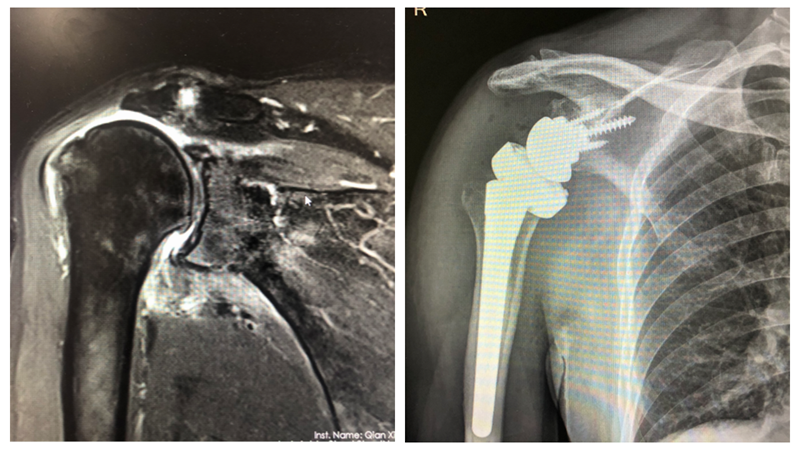

近日,黔西南州人民医院关节外科收治了一名复杂肩病患者,并采用新技术——反式肩关节置换手术,使患者彻底告别肩关节疼痛且不能活动的痛苦。这也是我院自2021年5月以来,成功开展的第4例“反式肩关节置换术”,拯救了患者“报废”的肩关节,手术效果满意,达到省级先进水平。意味着医院在肩关节外科领域技术的又一重大突破,也为广大受肩关节疾病困扰的患者带来了福音。

肩关节是人体活动度最大的一个关节,任何损伤都会对人体活动造成巨大影响。在不到一年的时间里,黔西南州人民医院关节外科相继收治了3例严重外伤导致肱骨头neer Ⅳ型粉碎性骨折困难修复肩关节功能患者,1例为巨大肩袖损伤关节镜、肌瓣无法修复,肩关节患者。

人工反肩关节置换术是把肩关节假体的球形关节面置于关节盂侧,而盂杯置于肱骨近端,与正常盂肱关节配对形成相反,“反转装”的目的能更好的发挥肩关节三角肌的动力性作用,完成肩关节需要的前屈上举、外展外旋、内收内旋等功能,从而降低降低肩关节对肩袖的依赖获得功能、疗效显著。

反肩置换术,手术难度大、风险高,能开展此项手术的医院较少,我省仅少数几家医院开展,病例不多。吴军主任详细研究病情,为患者制定了个性化、科学的诊疗方案,在麻醉科医师的配合下,带领张蜀平、姜文凯副主任医师等团队成员共同实施。手术达到预期效果,在程婧护士长团队的精心护理下,目前患者身体恢复情况良好。